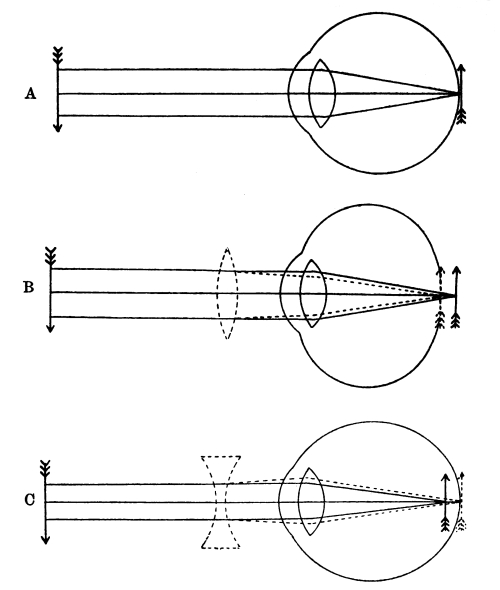

| 32. | Formation of an Image on the Retina | 391 |

| 33. | The Form of the Eyeball in Short Sight, Normal Sight,and Long Sight | 392 [Pg x] |